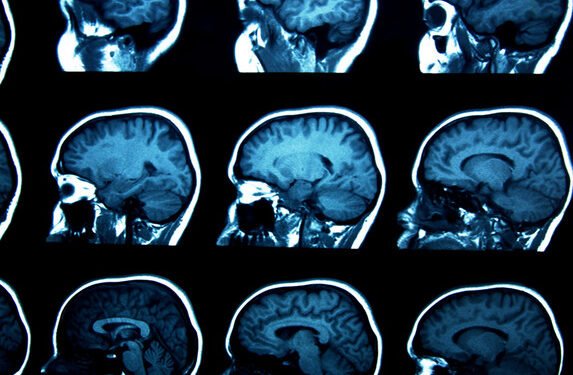

Titulado Lauriet, este estudio realizado junto a Genentech, filial estadounidense del gigante farmacéutico suizo Roche, busca evaluar este tratamiento que tiene como objetivo una parte de la proteína tau. En las taupatías (enfermedades neurodegenerativas) como la enfermedad de Alzheimer, la proteína tau se repliega mal y forma enredos que provocan daños celulares y finalmente la muerte neuronal.

Se supone que la proteína tau anormal se propaga luego entre las neuronas, implicando progresivamente más zonas del cerebro. El semorinemab es un anticuerpo monoclonal antitau experimental y está concebido para ligarse a tau y reducir su propagación entre las neuronas, explica la empresa suiza en el comunicado.